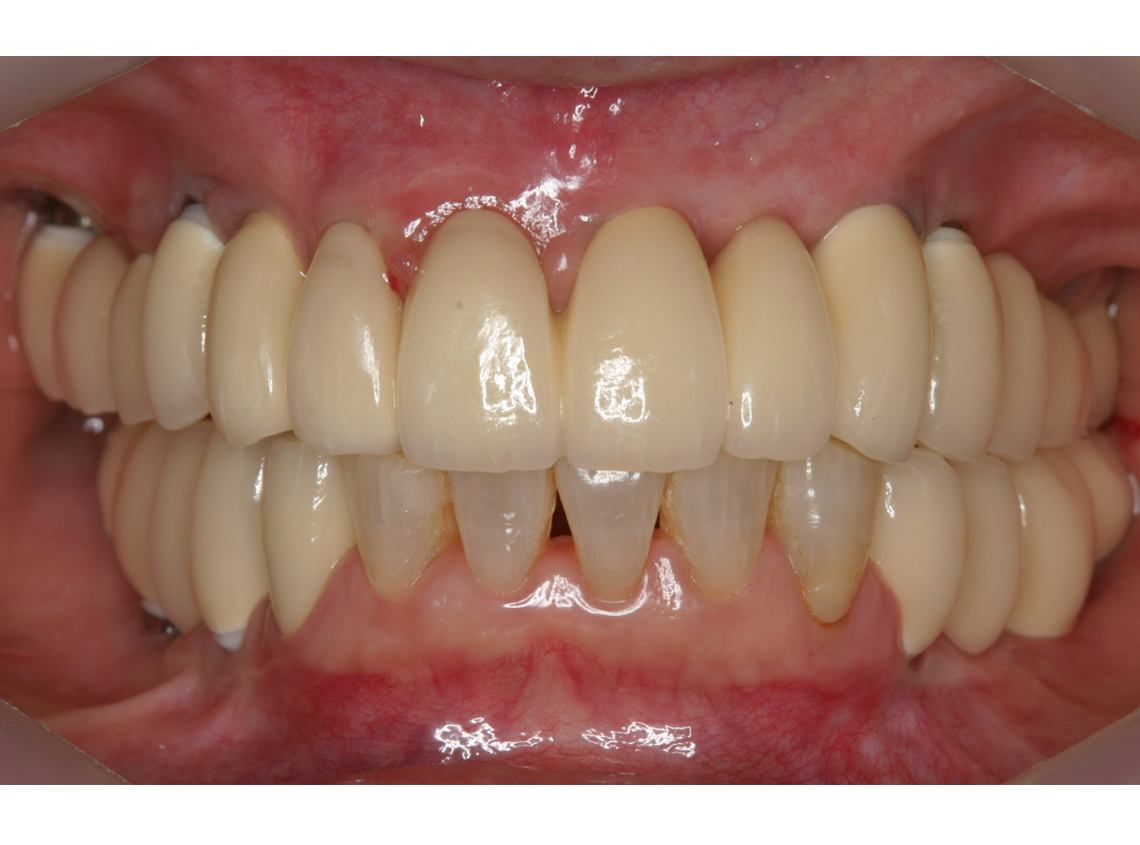

4.最終補綴物装着(2008年)

5.術後14年経過(2022年)

6.術後17年経過(2025年)

インプラント埋入部の骨レベルは埋入時と変わらず、患者様ご自身のメンテナンスも良好で、経過は非常に良く、満足されています。